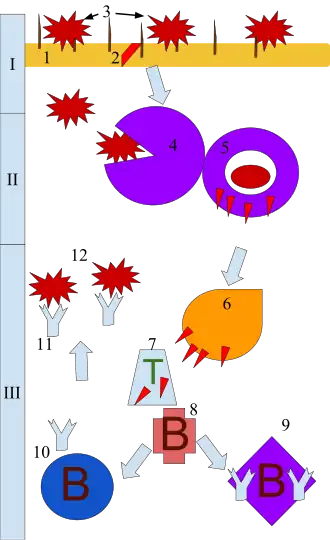

Mécanisme inflammatoire

Déclenchement

L'inflammation aiguë peut être considérée comme la première ligne de défense contre les blessures infligées à un tissu. Elle fait partie du système immunitaire inné.

Le processus d'inflammation aiguë est initié par les cellules immunitaires résidentes déjà présentes dans le tissu impliqué, principalement les macrophages résidents, les cellules dendritiques, les histiocytes, les cellules de Kupffer et les mastocytes. Ces cellules possèdent des récepteurs de surface appelés récepteur de reconnaissance de motifs moléculaires (PRR), qui peuvent reconnaître (c'est-à-dire se lier à) deux sous-classes de molécules, qui agissent comme signal déclencheur :

Phase cellulaire

À l'issue de la phase vasculaire ou vasculo-exsudative, la phase cellulaire fait suite à la diapédèse, lorsque les leucocytes sont amassés dans le tissu interstitiel.

Elle correspond à la formation du granulome inflammatoire[Note 1]. Il participe à la détersion (rôle des granulocytes et des macrophages) et permet le développement de la réaction immunitaire adaptative. Les cellules composant le granulome ont également un rôle de sécrétion de médiateurs chimiques.

Les leucocytes engloutissent les microbes et les détruisent, générant la production de pus. Le pus sera éliminé vers l'extérieur si la lésion est en contact avec l'extérieur, ou il générera un abcès si la zone où s'est formé le pus est à l'intérieur d'un organe.

La réparation des lésions tissulaires s'effectue grâce aux macrophages, qui stimulent les fibroblastes pour synthétiser le collagène et les cellules endothéliales pour générer de nouveaux vaisseaux, grâce à la sécrétion de facteurs de croissance.